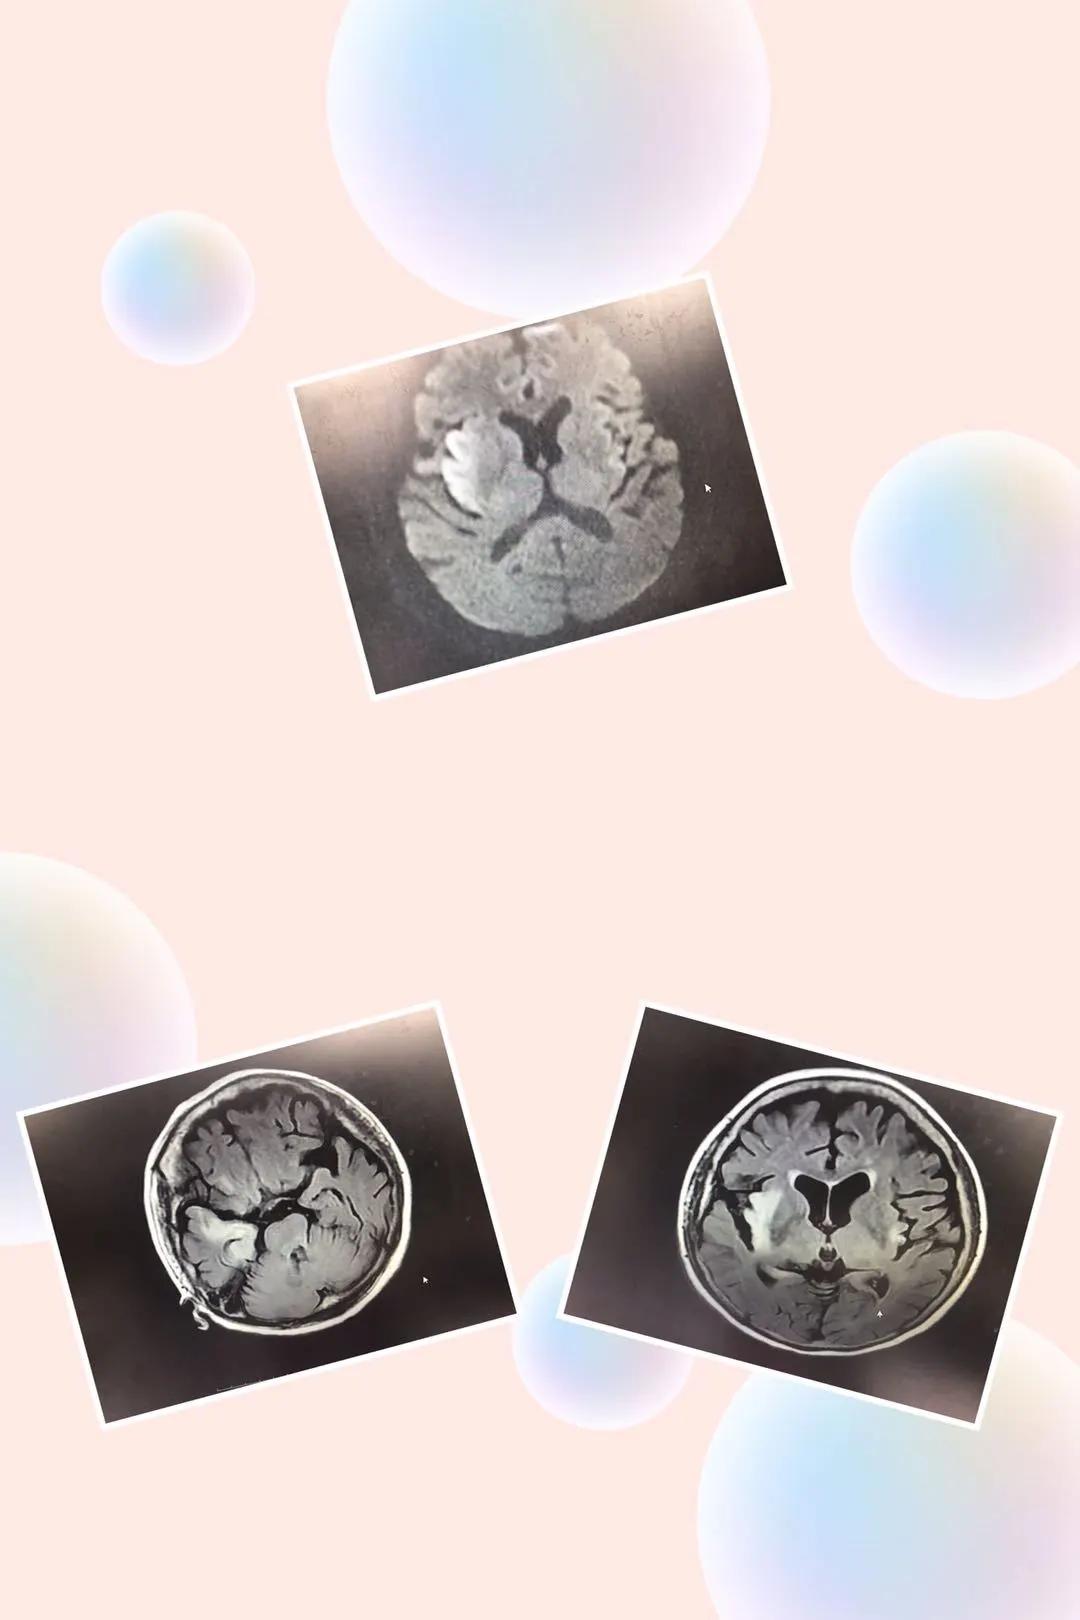

但事情的发展却不尽人意,马阿姨还是持续发热,神志转为嗜睡,出现幻视幻听,因头颅核磁检查发现颅内病变严重,血液相关检查出现许多异常,医生立即将马阿姨转进了重症监护室继续治疗。